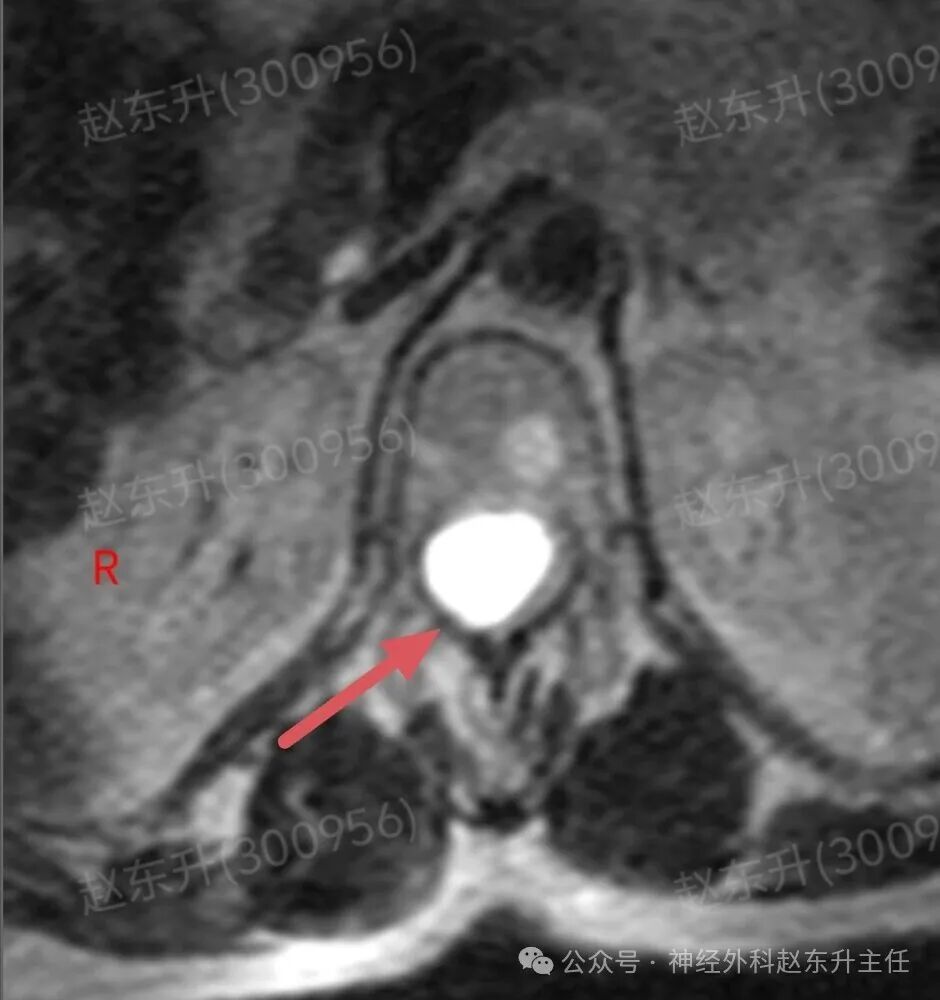

上周门诊来了一位58岁女性,患者因为下肢和腰背部顽固性疼痛半年,在各大医院就诊曾行针灸按摩,艾灸电疗等治疗没见缓解,而且疼痛评分可以达到8-9分,口服止痛药无效,康复理疗无效。随后查了一下腰椎磁共振,发现胸12腰1节段脊髓内异常信号,随后收入我科。入院之后查肌电图提示下肢和骶神经损伤严重,随后我们在全麻下使用显微镜,并且术中电生理监测下,给予脊髓内肿瘤次全切除,术后病理提示是胶质瘤。术后第2天我们就给他用了经颅磁刺激等神经康复治疗,虽然术后第1天右下肢肌力较术前减退,但经过10天的治疗以后,下肢肌力逐渐恢复,可以下地行走了。术后他还需要进一步的放疗和化疗来抑制肿瘤的生长,预防肿瘤复发。

图片图片图片图片图片图片图片图片切除的肿瘤图片术后病理西安市红会医院神经外科赵东升主任介绍:脊髓内胶质瘤是一种起源于脊髓实质内部的胶质细胞(即神经系统的“支持”细胞)的肿瘤。与脊膜瘤(位于脊髓外)的关键区别在于,它生长在脊髓内部,因此会浸润并破坏正常的脊髓神经组织核心特征:性质:涵盖从低级别良性到高级别恶性的完整谱系,但以低级别为主。位置:完全位于脊髓中央,可累及多个脊髓节段,甚至全长脊髓。特点:肿瘤与正常脊髓组织边界不清(浸润性生长),手术全切极为困难。其生长直接破坏神经传导束,导致严重神经功能障碍。发病率:相对少见,约占所有中枢神经系统胶质瘤的2-4%,但却是儿童最常见的髓内肿瘤。无明显性别差异。与脊膜瘤的关键区别总结

主要类型1.室管膜瘤(约占60%):常见的成人髓内胶质瘤。多为低级别(WHO I级和II级),生长缓慢。常发生于颈段和胸段,常有明确边界,有时可有“假包膜”,是手术全切希望最大的一种。2.星形细胞瘤(约占30%):常见的儿童髓内胶质瘤。从低级别(毛细胞型星形细胞瘤,WHO I级,预后好)到高级别(胶质母细胞瘤,WHO IV级,预后极差)都有。浸润性生长为特点,与正常脊髓几乎无边界,手术全切风险极高。3.其他少见类型:如血管母细胞瘤(常与VHL病相关)、少突胶质细胞瘤等。临床表现(症状)症状因肿瘤生长缓慢而隐匿、渐进性加重,早期易被忽视。典型症状:1.感觉障碍(最早、最常见):l分离性感觉障碍:这是特征性表现。由于肿瘤侵犯脊髓中央的白质前连合,导致痛觉、温觉纤维受损,而触觉、深感觉保留。患者表现为双侧对称性的、节段性的痛温觉减退或消失,而触觉正常l麻木、酸痛、束带感。2.运动障碍:n肿瘤平面以下出现肢体无力、僵硬、肌肉萎缩(尤以手部小肌肉萎缩常见)。n行走困难,步态不稳。3.疼痛:定位不明确的颈背部疼痛,夜间痛可能更明显。4.自主神经功能障碍(晚期):l大小便失禁或困难。l性功能障碍。l皮肤营养障碍(无汗、皮肤干燥等)。诊断增强磁共振(MRI): 是首选和确诊的关键检查。典型表现:可见脊髓呈梭形、偏心性或中心性增粗。肿瘤在T1像呈等或低信号,T2像呈高信号,增强后强化模式多样(可均匀、不均匀或环形强化)。可清晰显示肿瘤范围、有无囊变、脊髓空洞等。CT:价值有限,主要用于评估是否有脊椎骨质改变。治疗治疗远比脊膜瘤复杂,需在多学科团队(神经外科、肿瘤科、放疗科)指导下进行个体化综合治疗手术治疗(首要且核心):l目标:在最大限度保护神经功能的前提下,实现最大安全程度的肿瘤切除。全切是目标,但常因肿瘤边界不清而无法实现。l技术:在术中神经电生理监测(监测运动、感觉传导束功能)的保驾护航下,使用显微外科技术、超声吸引、激光等进行精细操作。功能保护优先于肿瘤全切放射治疗:主要适用于:高级别胶质瘤术后辅助治疗、无法全切的低级别胶质瘤术后残留、肿瘤复发无法再次手术者。化学治疗:l对于高级别(恶性)脊髓胶质瘤,可参照脑胶质瘤方案进行化疗(如替莫唑胺)。l对于部分复发的低级别胶质瘤也可能使用。预后与随访预后差异巨大,高度依赖于肿瘤的病理类型和分级l低级别室管膜瘤:若能实现全切,预后良好,可达到长期无进展生存,甚至临床治愈。复发率低。l低级别星形细胞瘤(如毛细胞型):全切后预后也很好。次全切后也可能长期稳定。l高级别胶质瘤(如胶质母细胞瘤)预后极差,即使积极治疗,也极易在脊髓内播散复发,生存期短。l随访:术后需定期(通常每3-6个月,后逐渐延长)进行增强MRI复查,监测肿瘤是否残留或复发。神经功能康复治疗至关重要赵东升主任简介医学硕士,西安市红会医院北院区神经外科主任医师,从事神经外科近20年。使用独创的“三维一体疗法”成功促醒大量昏迷病人,使上百例脊髓损伤瘫痪患者重新站起来。最早在陕西省开展第一例脊髓电刺激治疗昏迷病人,第一例脊髓电刺激手术治疗截瘫病人,第一例脊髓电刺激手术治疗下肢缺血顽固性疼痛。主编专著3部,参编专著11部,发表学术论文30余篇,荣获国家专利32项(其中四项发明专利),担任多部杂志编委及审稿专家。擅长:1.脑病方面:昏迷促醒,脑肿瘤、脑积水、脑梗死偏瘫、肌张力增高、顽固性癫痫、三叉神经痛、脑干出血、老年痴呆、帕金森、头痛等;2.脊髓病方面:脊髓损伤、脊柱术后疼痛、大小便障碍、脊髓肿瘤、脊髓空洞、小脑扁桃体下疝畸形、脊髓栓系、脊膜膨出、痉挛性截瘫等;3.周围神经疾病方面:糖尿病足、下肢缺血性疼痛、臂丛神经损伤、腓总神经损伤、腕管综合征、肘管综合征、男性功能障碍等门诊时间:北院区:周一全天门诊二楼203A  第五诊室南院区:周二全天门诊三楼310诊室